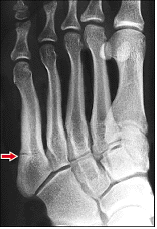

The fifth metatarsal is basically the bone that connects to the little toe on the left side of my left foot.

The peronial tendon is the tendon that wraps behind the ankle and connects to the fifth metatarsal. Peroneal tendonitis is the inflammation of that tendon.